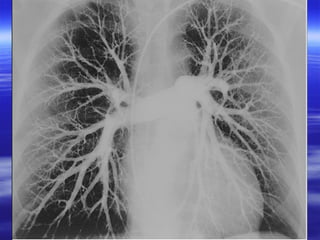

PPuullmmoonnaarryy aannggiiooggrraapphhiicc ffiinnddiinnggss

PPrriimmaarryy ssiiggnnss::

TThhee oonnllyy pprriimmaarryy ssiiggnn ooff aaccuuttee ppuullmmoonnaarryy

eemmbboolliissmm iiss ffiilllliinngg ddeeffeecctt..

SSeeccoonnddaarryy ssiiggnnss::

AAbbrruupptt oocccclluussiioonn ooff ppuullmmoonnaarryy aarrtteerryy..

AArreeaass ooff oolliiggeemmiiaa wwiitthh pprruunniinngg ooff tthhee

bbrraanncchhiinngg vveesssseellss..

PPuullmmoonnaarryy aannggiiooggrraapphhiicc ffiinnddiinnggss PPrriimmaarryy ssiiggnnss:: TThhee oonnllyy pprriimmaarryy ssiiggnn ooff aaccuuttee ppuullmmoonnaarryy eemmbboolliissmm iiss ffiilllliinngg ddeeffeecctt.. SSeeccoonnddaarryy ssiiggnnss:: AAbbrruupptt oocccclluussiioonn ooff ppuullmmoonnaarryy aarrtteerryy.. AArreeaass ooff oolliiggeemmiiaa wwiitthh pprruunniinngg ooff tthhee bbrraanncchhiinngg vveesssseellss..